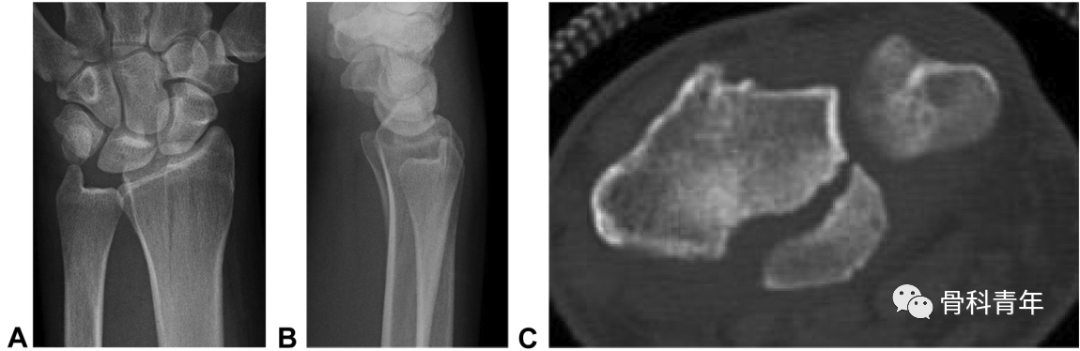

“四面体”型桡骨远端骨折概念:桡骨远端部分关节内骨折,骨折累及桡骨掌尺侧关节面及乙状切迹,横断位上呈三角形,骨折线延伸至桡骨干骺端。该骨折的特殊性体现在桡骨掌尺侧骨块的特殊性。一方面,掌尺侧骨块形成的月骨窝,作为抵抗腕骨向掌侧脱位的物理支撑,该结构的支撑作用消失导致腕关节掌侧脱位;第二,该骨块作为下尺桡关节桡骨关节面的组成部分,恢复其解剖位置是恢复下尺桡稳定性的前提。下图示病例1:典型“四面体”型桡骨远端骨折的影像表现。

在5年的病例中,研究中发现7例该类型骨折。在手术指征上,对上图病例1在内的3例无移位骨折病例,初次行保守治疗,但在随访过程中均出现骨折移位,而进行内固定手术;提示该类型骨折的不稳定性高,再移位风险高,手术指征强。在治疗上,2例采用传统桡侧腕屈肌入路钢板螺钉内固定,其中1例内固定失效骨块移位,采用掌尺侧入路,柱钢板特异性固定中柱翻修。出现内固定失效病例后,其后的5例病例均采用掌尺侧入路2.0mm或2.4mm钢板固定